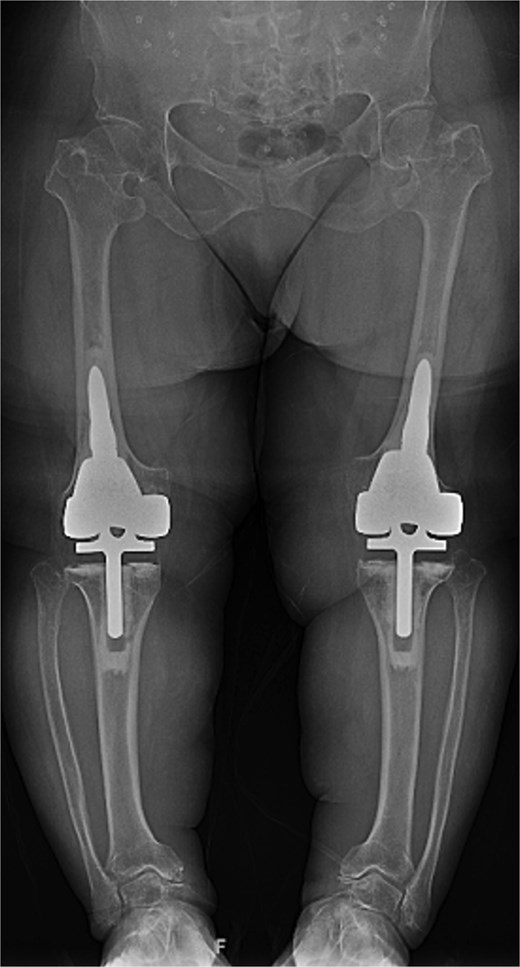

At the 2-year follow-up, the patient reported no significant pain, demonstrated a normal gait, and had active bilateral knee range of motion from 0° to 125°. There was no joint line tenderness or instability. Surveillance radiographs confirmed well-aligned and stable components with no evidence of implant failure or periprosthetic lucency (Fig. 3). At the five-year follow-up, the patient remained very satisfied with her knees and denied knee pain. On exam, her gait was slightly antalgic, but active bilateral knee range of motion remained preserved at 0° to 120°, and both knees remained stable throughout range of motion and nontender to palpation. Radiographs continued to show stable prosthetic components without evidence of implant failure or periprosthetic lucency (Fig. 4).

Five-year postoperative AP radiographs showing continued stability of bilateral rotating-hinge implants with maintained alignment and no radiographic evidence of implant failure.